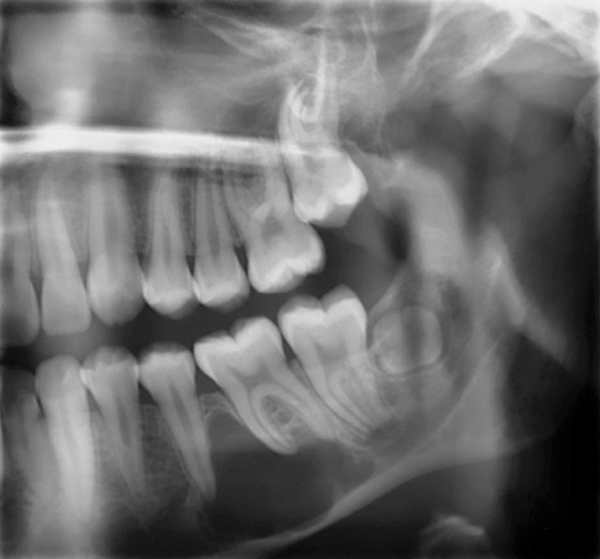

Figure 1 Traditional intraoral bitewing showing limited field of view (Fig 1) compared to the expanded view possible using CBCT (Fig 2).

Figure 1

Figure 2 Traditional intraoral bitewing showing limited field of view (Fig 1) compared to the expanded view possible using CBCT (Fig 2).

Figure 2

CBCT can also be used in this same manner to perform an even more common task, bitewing images, which are clinically indicated as often as every 18 to 24 months. For hygiene patients whose films require updating, CBCT offers a “patient-friendly” approach. Given that these films, which are usually performed intraorally, are often taken on an hourly basis in the typical general practice, the technology can be well utilized while also increasing comfort and satisfaction among patients. In addition, due to the expanded field of view that can be achieved with these extraoral CBCT images, they can often be more diagnostically valuable than images produced with an intraoral sensor (Figure 1 and Figure 2).